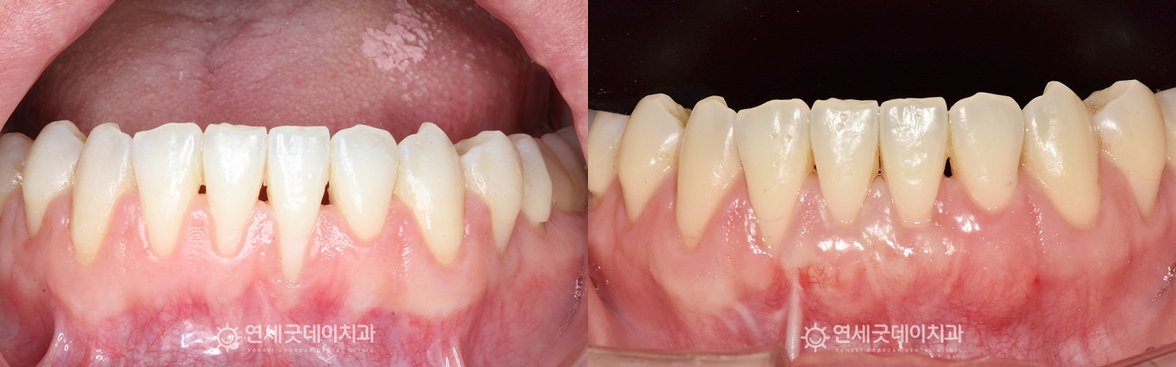

입천장에서 잇몸조직을 채취한 뒤,

잇몸이식수술 후 10일 뒤 경과 체크 당시 모습입니다. 이식 부위가 잘 아물면서 두툼한 잇몸이 형성되는 양상을 확인할 수 있었습니다.

한 달 뒤에는 수술 부위가 안정적으로 치유되어

약 8개월 간의 부분교정과 잇몸이식수술을 통해 치주교정은 치열과 잇몸 문제가 동시에 관찰될 때, 치료 받으시느라 고생 많으셨습니다. ^^ ※ 모든 사진은 본인의 동의를 얻어 동일조건에서 촬영하였으며 |